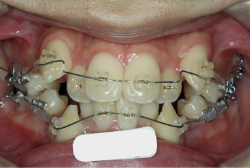

成長発育期の叢生症例・非抜歯治療

今回は「歯並びの凸凹を治したい」という主訴で来院したケースです。診断の結果、「成長発育期の叢生」と判明しました。叢生とは歯並びの凸凹のことですが、この方の場合は上顎が少々重症で、上の犬歯が外側へ飛び出し、いわゆる「八重歯」という状態でした。凸凹の解消のためには永久歯を抜歯して隙間を作って残った歯をきれいに配列する方法(抜歯法)と、歯列を拡大して配列する方法(非抜歯法)の2種類があります。歯列の拡大にはさらに2つの方法が有り、横方向へ拡大する場合と、臼歯を後方に移動させて拡大する方法があります。今回の症例のようなケースでは、横方向へ拡大してもあまり効果的ではなく、後方への移動が最適です。上の臼歯を後方へ移動させるために、今回はヘッドギヤという取り外し式の装置を、夜寝る時に半年ほど使用していただきました。

注意点としてここでお伝えしたいのは、矯正専門医ではない歯科医院で、いわゆる「床矯正」という方法を行うと、たいてい横方向の拡大になってしまいます。無駄に横方向の拡大をするとかえって症状を悪化させたり、何の効果もないことになってしまいます。一見簡単そうな矯正に見えたとしても、しかるべき矯正専門医に診断してもらうことをおすすめします。

この方の場合、治療期間はヘッドギアを6ヶ月、マルチブラケット法を7ヶ月でした。治療後は凸凹が改善しただけでなく唇の審美性が大幅に改善しました。もちろん噛み合わせ的にも正しい状態が確立しています。